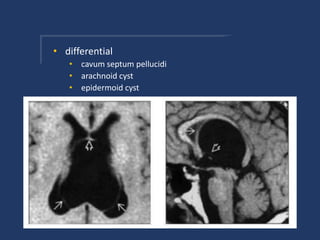

• differential

• cavum septum pellucidi

• arachnoid cyst

• epidermoid cyst